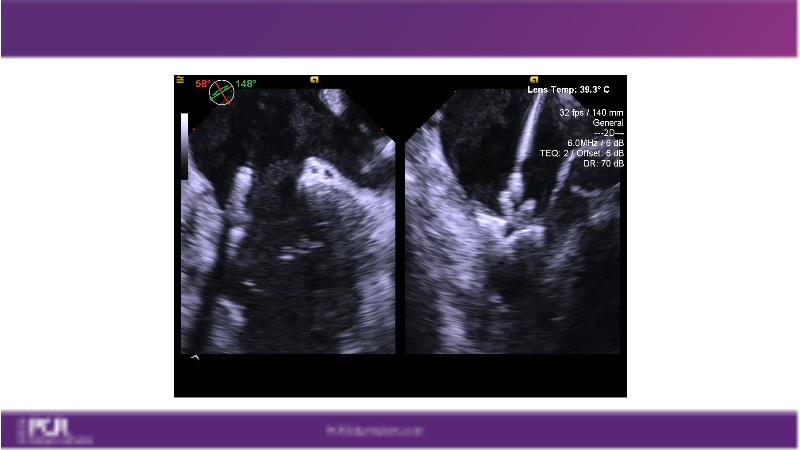

Watch this session to get an overview of a new TEER device, follow the step-by-step procedure related to initial experiences with this device for a Japanese patient with degenerative mitral regurgitation, learn about the latest data from RCT and registries, and follow discussions of challenging TEER cases!

- To learn procedural step-by-step of novel device